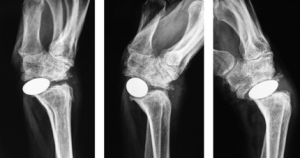

Pyrocarbon Wrist Replacement

Pyrocarbon joint replacement surgery for end stage wrist arthritis is a good alternative to traditional total wrist arthroplasty or fusion.

This implant, called the Amandys, is a large pyrocarbon pebble that acts as a “spacer” device to maintain wrist joint height and soft-tissue tension, thereby preserving wrist motion and treating painful arthritis. Wrist motion can be relatively well preserved compared to fusion (see below).

A good alternative to wrist fusion, which prevents further wrist motion.